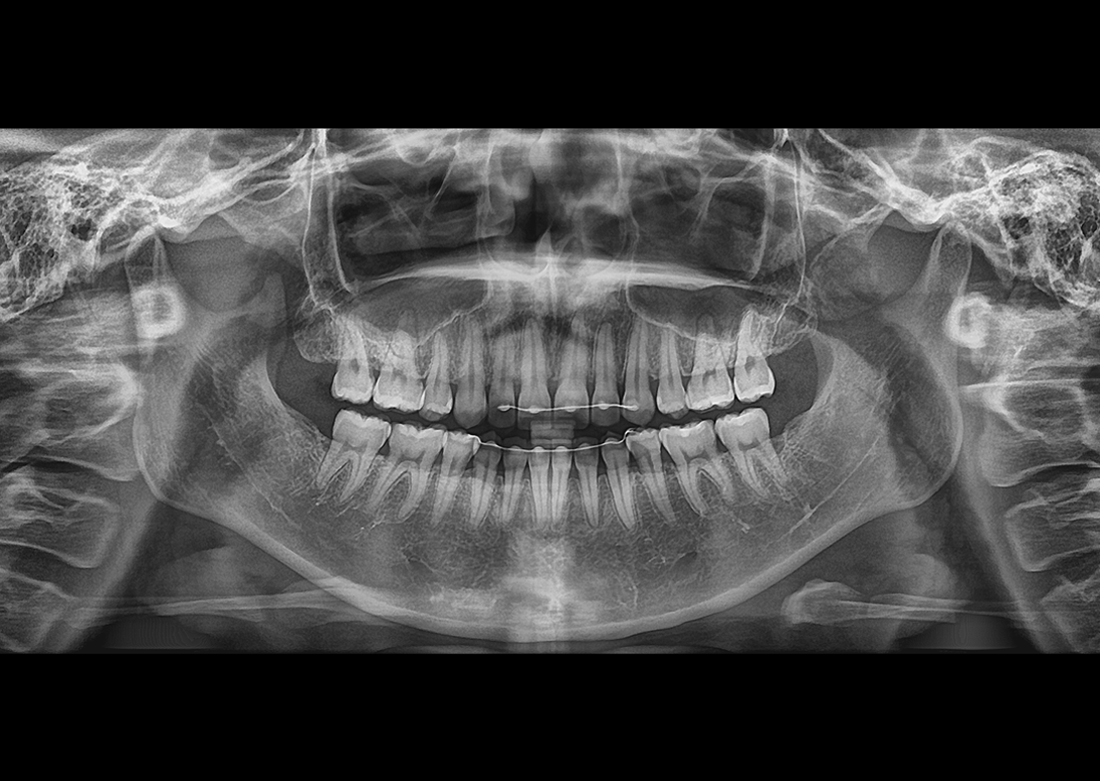

KLİNİK FOTOĞRAFLAR

Yılların tecrübesi ve geliştirdiği know-how teknolojileri ile muhteşem teşhis görüntüleri yaratmak Genoray firmasının herzaman gururu olmuştur..